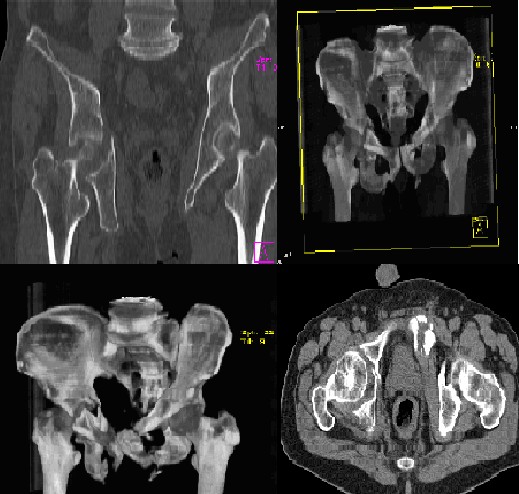

Дополнение:КТ и рентгенограммы ложного сустава таз

Максим 18 Март 2009, 21:15

Здраствуйте коллеги! Дополнениение информации к ложному сусатву костей таза: КТ сканы и рентгенограмма

Реногеноргаммы ложного сустава костей таза

Максим 18 Март 2009, 21:38

Уважаемые коллеги! Добавлены ренгенограммы ложного сустава костей таза

Основная проблема связана с переломом дна вертлужной впадины (боль в правом тазобедренном суставе), но имеется так же и нестабильное повреждение костей таза(разрыв левого крестцово-подвздошного сочленения с переломом ереднего полукольца). Насколько выражен болевой синдром при опоре на левую нижнюю конечность?Есть ли необходимость фиксировать тазовое кольцо? Что касается прелома дна вертлужной впадины, то предпочтительнее остеосинтез, однако операция весьма травматична, а прогноз сомнителен.